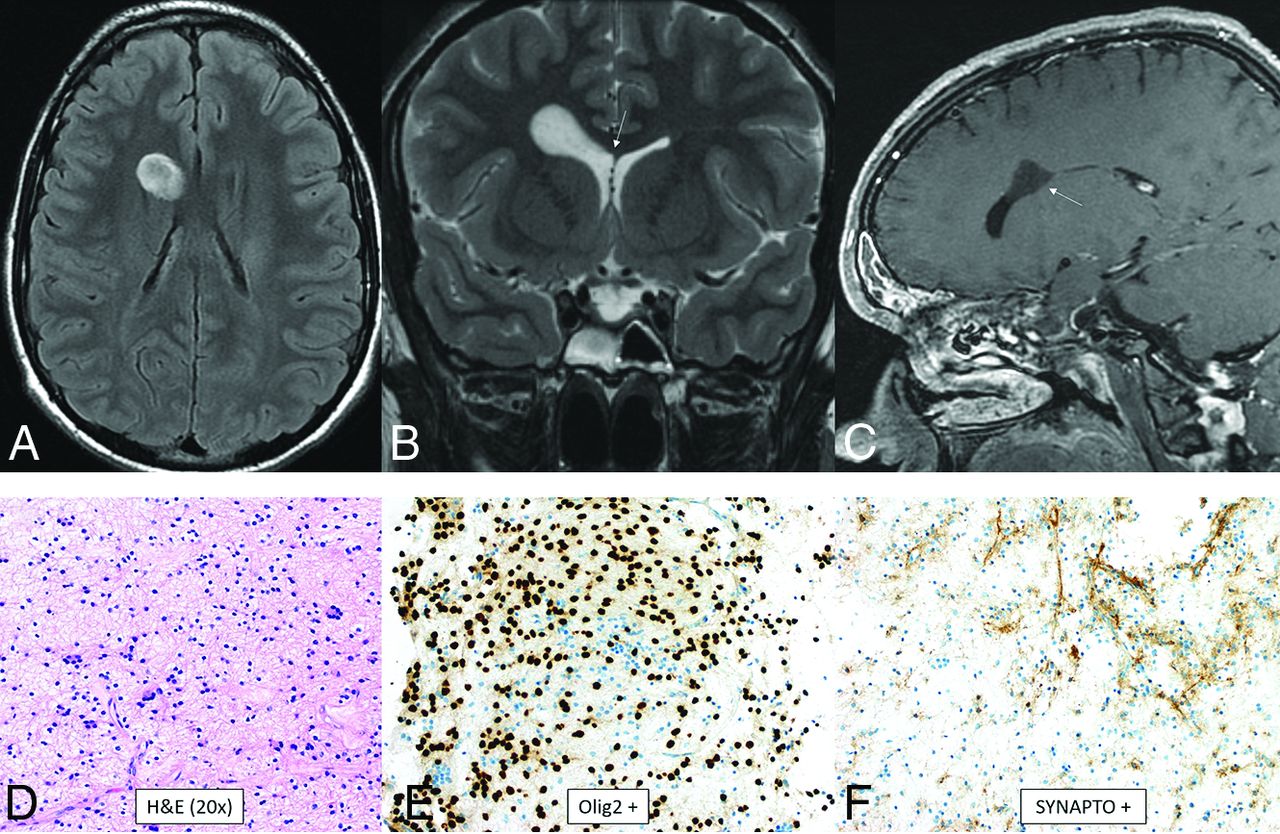

Myxoid Glioneuronal Tumor

Myxoid glioneuronal tumor is a benign WHO grade 1 tumor that shows low-grade oligodendrocyte-like tumor cells with a myxoid-/mucin-rich stroma on histology. A fine capillary network is sometimes present along with neurocytic rosettes. Glial fibrillary acidic protein (GFAP) and OLIG2 are positive. The defining feature is a PDGFRA p.K385 mutation. Abnormalities in FGFR1, IDH1/2, BRAF, MYB, and MYBL1 are absent.36,37 Data are limited, but in the largest described series, the median patient age was 23.6 years (range, 6–65 years) with no sex predilection.38 These tumors have a propensity for the septum pellucidum.36,38 A typical mass is well-defined, lobulated, T1-hypointense, T2-hyperintense, nonenhancing, non-diffusion-restricting, and without surrounding edema. T2-FLAIR shows relative hypointensity centrally and hyperintensity peripherally (Fig 8). There is no elevated CBF. Larger lesions can appear L-shaped and have mass effect, which can mimic high-grade tumors.36⇓⇓-39

Myxoid glioneuronal tumor. MR imaging shows a mass in the right frontal horn region with peripheral T2-FLAIR hyperintensity and relative central T2-FLAIR hypointensity (A), which is slightly hypointense to CSF on the T2-weighted image (B), approaches the septum pellucidum (arrow, B), and does not enhance (C). There is no adjacent edema. Histology shows an oligodendroglioma-like appearance with moderate cellularity and uniform round nuclei with a circumferential arrangement around delicate vessels (D). Immunohistochemical staining is positive for OLIG2 (E), synaptophysin (F), and GFAP and negative for NeuN. This tumor has a PDGFRA p.K385 mutation and lacks FGFR1 abnormalities. Dysembryoplastic neuroepithelial tumor is a histologic mimic but has a mutation of FGFR1.